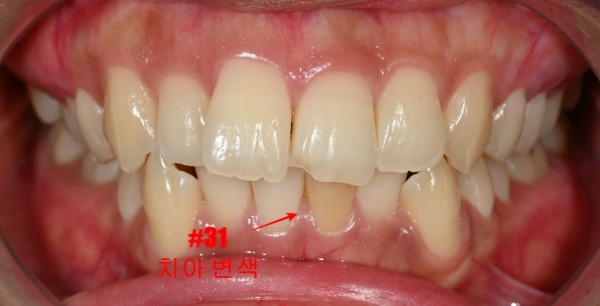

신경치료를 받은 치아가 변색되는 것은 사실 꽤 흔한 일입니다.

신경이 없어진 치아는 혈액 공급이 중단되면서 자연스럽게 색이 어두워지는 경우가 많거든요.

하지만 앞니 부위라서 미소 지을 때마다 눈에 띄어 스트레스를 받으셨다고 하시더라고요.